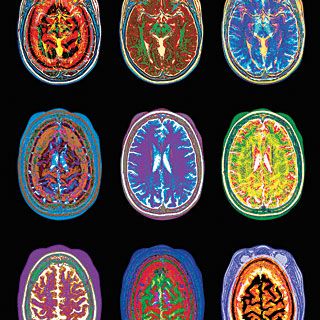

Перфузионная МРТ

Особенности магнитно резонансной перфузии головного мозга

Создание перфузионной МРТ головного мозга позволило изучать мелкие сосуды мозга, что стало основой для раннего выявления ишемии (недостаток кислорода), небольших опухолей, атеросклеротического, неврогенного спазма сосудов, мигрени.

Обследование выявляет не только интенсивность сигнала, отражающего объем крови при прохождении по капилляру, но и среднее время распространения контраста по сосуду. Анализируя показатели перфузии головного мозга, программное приложение создает кривые накопления, показывающие скорость кровообращения в определенных участках мозга через определенные промежутки времени.